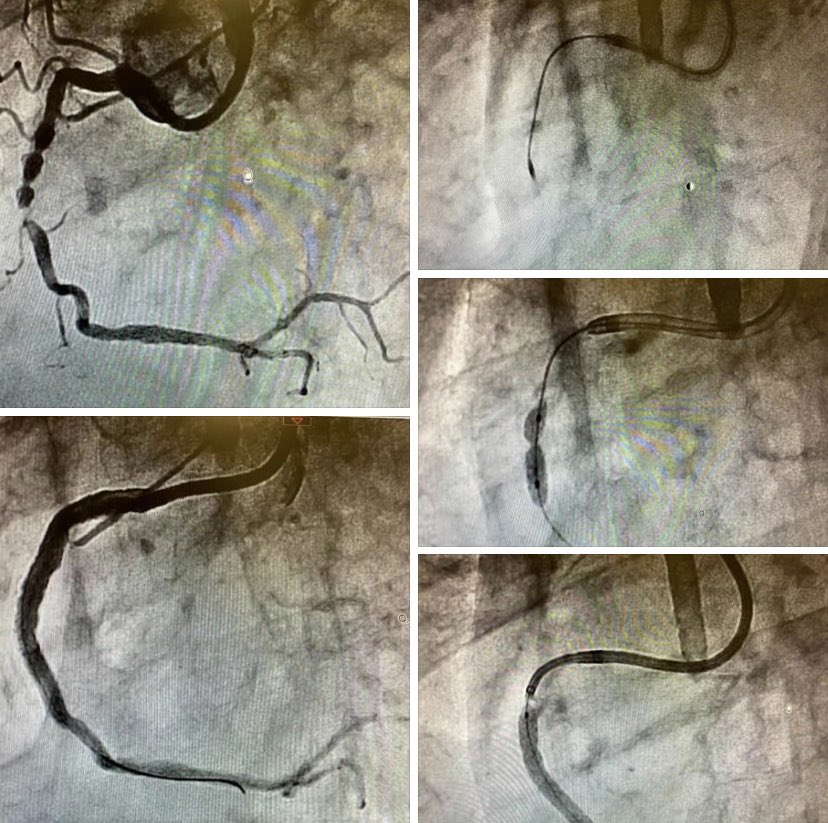

All our possibile tools to treat a severely calcified non crossable and non dilatable lesion: Rotablator, Shockwave and Guide Extension Catheter. Rimini Cath Lab.